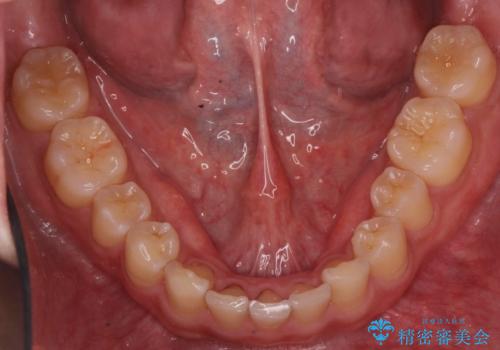

上下のかみこみがきつい場合で上にだけすき間がある場合は、上のすき間を閉じきるのは難しいことが多いです。

理由としては、すき間を閉じるには上の前歯は後ろに下がる形に動かないと無理なのですが、かみこみがきつい(かみ合わせがきつい、上下が深く咬んでいるともいいます)場合は、すぐ後ろに下の歯がかみこむためその動きができないためです。

さらに下の前歯にがたつきがある場合は下の前歯を後ろに下げること自体が難しくなるため、生まれつき歯の形が特殊な場合は、上のすき間を適切な位置にずらして、しかるべき歯にセラミッククラウンを被せて形態修正とスペースを埋めるというのが効率の良い治療方法と言えます。